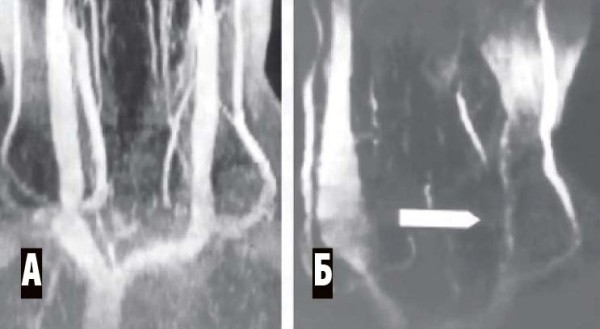

При дорсопатии: лучевая диагностика — МРТ позвоночника, шейная спондилография (обязательно 5 проекций, включая трансоральную спондилограмму), а также

МР-венография брахиоцефальных вен (см. рис. 6).

Рисунок 6. МР-венограмма. Мышечная компрессия внутренней яремной вены. А — брахиоцефальные вены в норме, Б — сдавление левой внутренней яремной вены гипертрофированными нижними шейными мышцами (уровень сдавления показан стрелкой). Противоположная внутренняя яремная вена компенсаторно расширена.